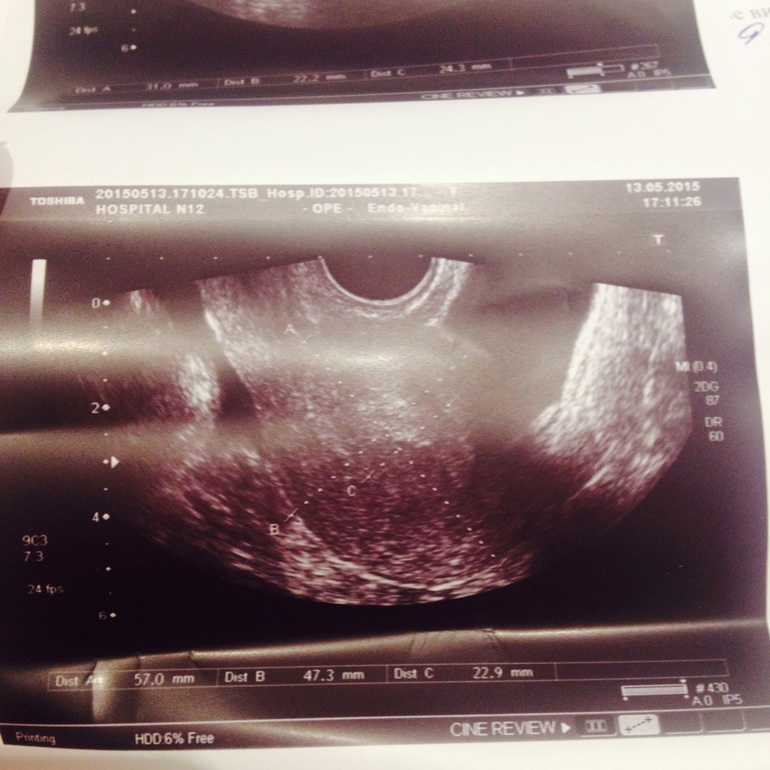

Сегодня ходила к врачу. Врач проверенный и хороший (записывалась через знакомых). Сделали узи. Эндометрий хороший, толстый. Ничего "криминального" не нашли. Плодное яйцо, конечно, пока не увидели...рановато. Врач сказала завтра пересдать хгч, на повторное узи через 10 дней. Говорит, что, возможно, организм только готовится к беременности. То есть, вот-вот может случиться, туманный альбион какой-то((( В общем, ничего не ясно. Буду ждать.

Фото узи под катом... что-то там отметили.